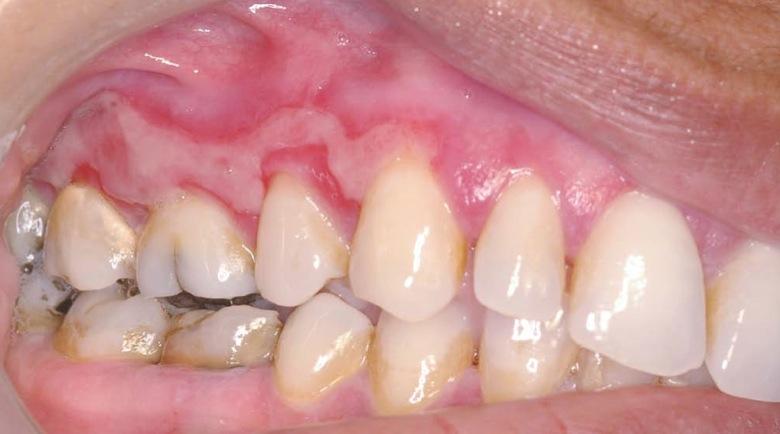

Descripción del caso Una mujer de 44 años acude a su dentista por la presencia de, según ella misma denomina, llagas en sus encías desde hace unos seis meses. Pese a...